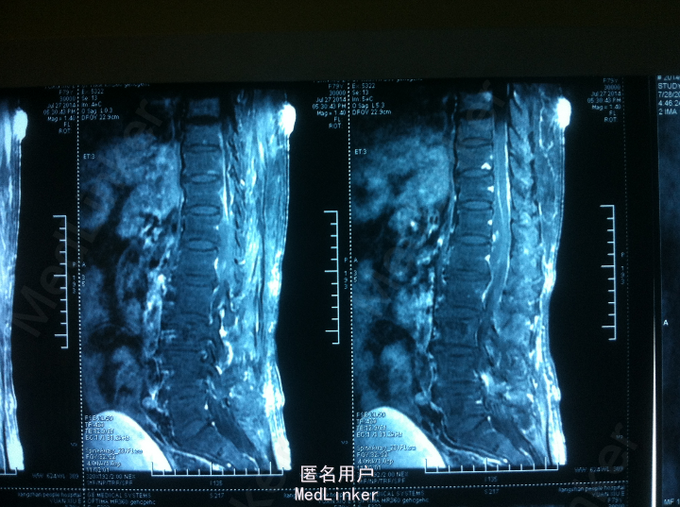

查体:腰部叩痛,双下肢感觉减退,双下肢肌力2-3级,双侧膝跟腱反射未引出,肌张力减弱,巴氏征未引出。 CT:腰椎硬膜外血肿可考虑 MR:腰椎硬膜外血肿

诊断:自发性腰椎硬膜外血肿 患者入院后给予甘露醇、甲泼尼龙、甲钴胺、神经节苷脂等药物,第二天,双下肢麻木较前减轻,双下肢肌力3-4级,与患者及家属沟通后,患者家属拒绝手术减压血肿清除,继续给予消肿、营养神经药物治疗,入院第5天,患者双下肢麻木明显消失,双下肢肌力4-5级,好转出院。

术后1个月,患者双下肢无明显麻木,双下肢肌力4-5级。患者家庭经济原因,未查腰椎MR。 讨论:1、自发性硬膜外血肿的原因 ?血管因素、高血压? 2、自发性硬膜外血肿手术指征把握,积极手术清除减压或保守观察?